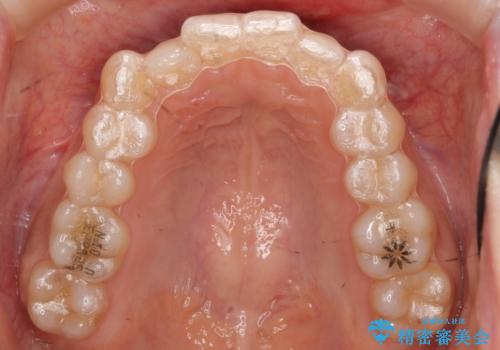

- 矯正装置

- インビザライン

- 右上の犬歯のねじれ、下の歯のがたつきを主訴に来院。

インビザラインで歯を抜かずに並べました。

初回:上顎16ステージ 下顎22ステージ

リファインメント: 上顎23ステージ 下顎20ステージ

下の前歯のがたがたがそれなりにあったため、リファインメントを行いました。